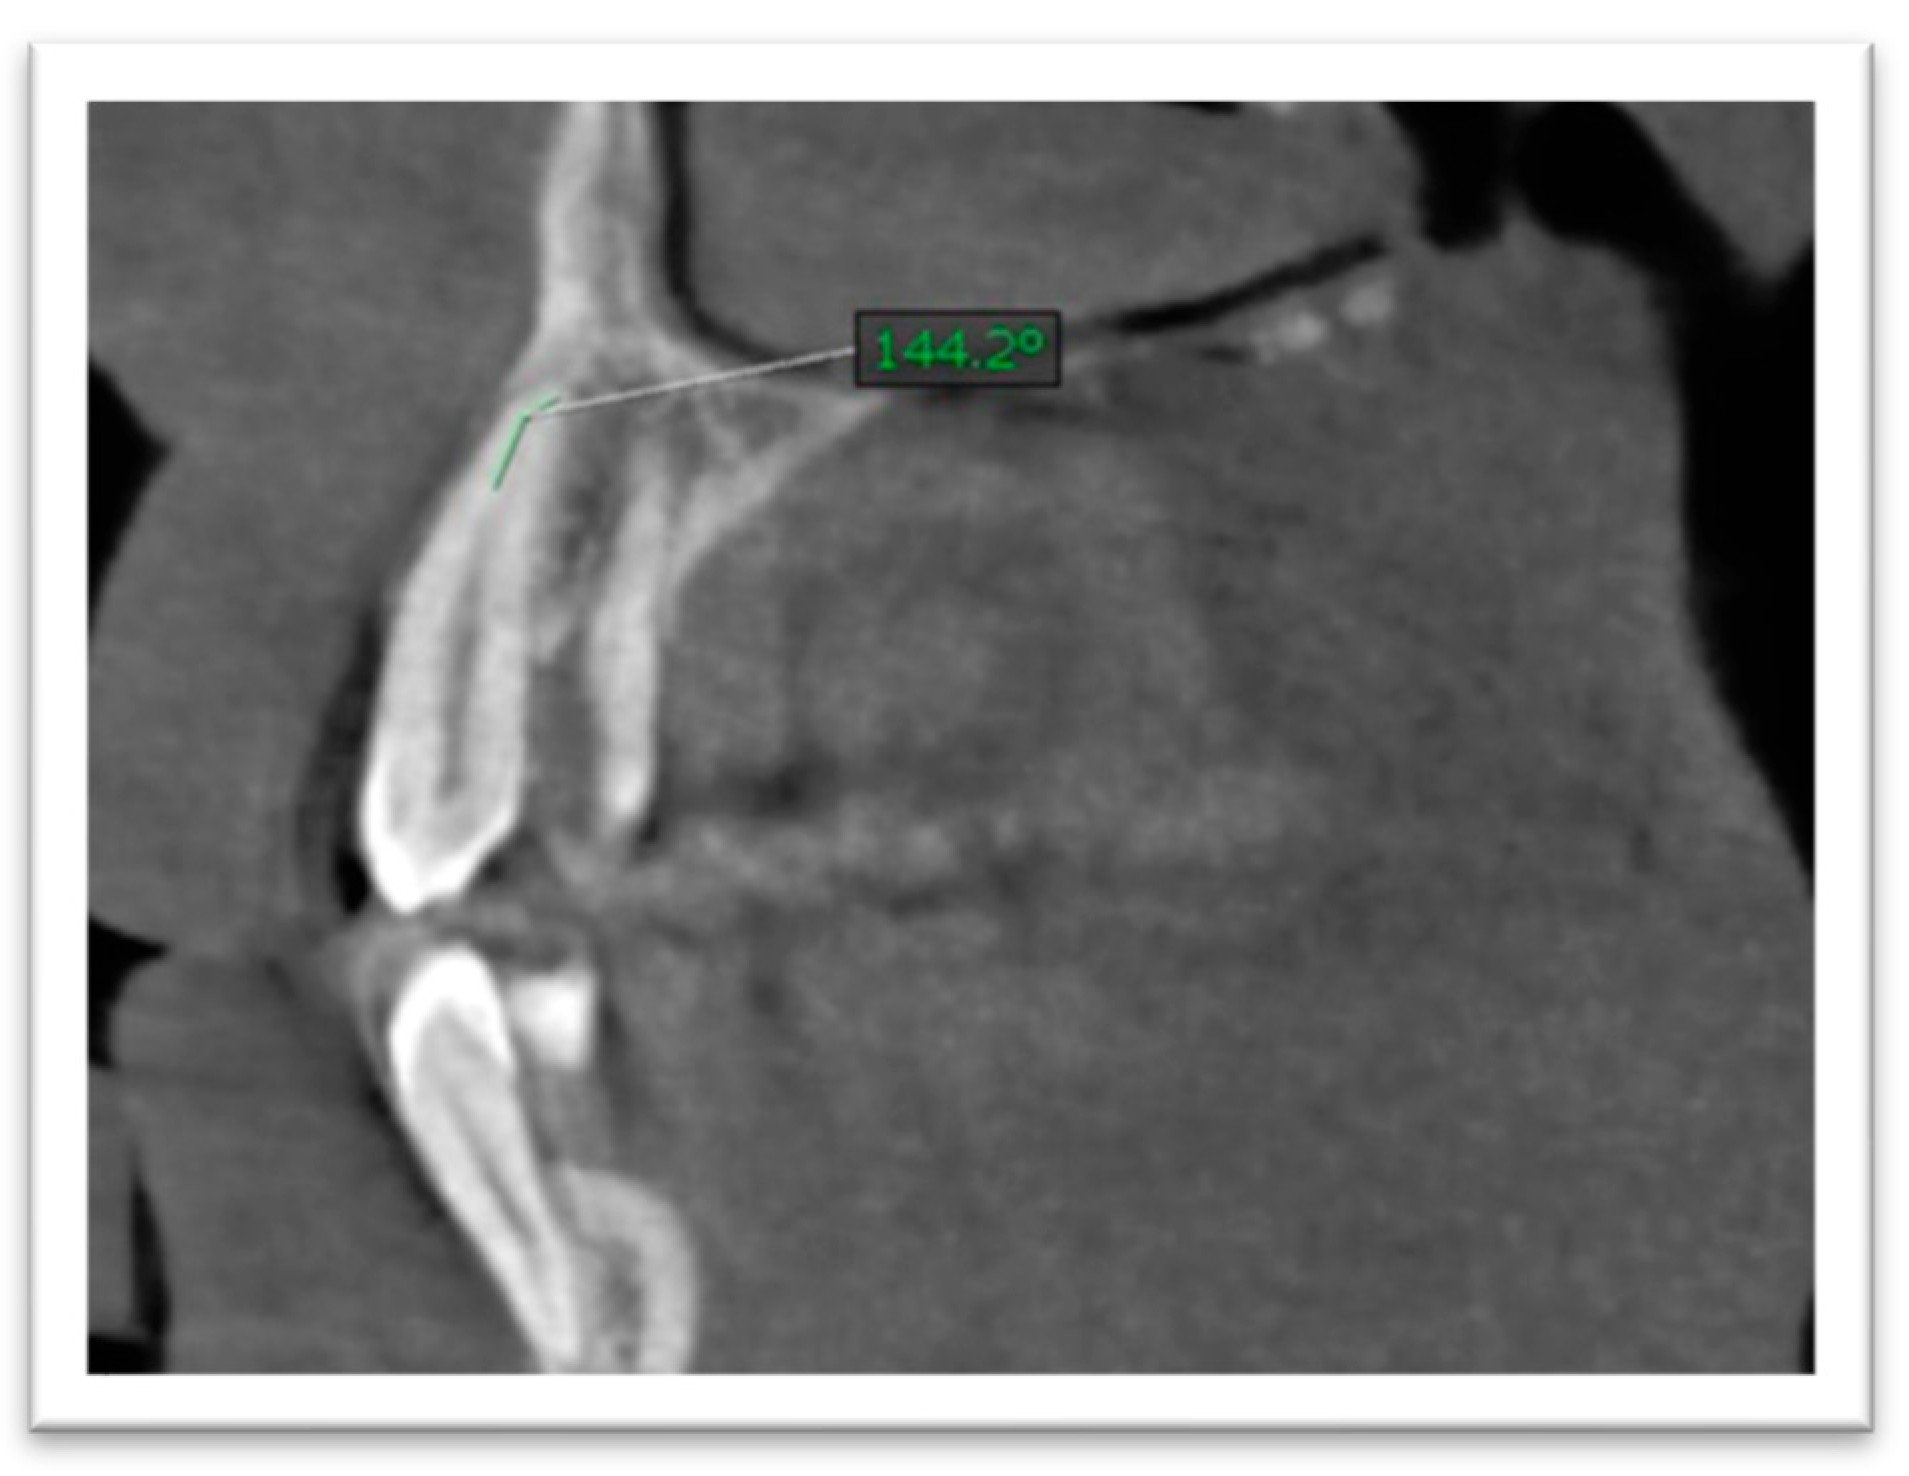

- (4)

- Since root length was recorded as a straight-line distance, it may slightly underestimate true anatomic length in teeth with pronounced curvature; standardized reorientation was used to capture the maximum tooth length on the plane of measurement. Root canal curvature (angulation) was assessed by scrolling through sagittal and coronal planes. The curvature angle was measured using a Schneider-type approach: a first line was drawn parallel to the canal in the coronal third, and a second line was drawn from the point where the canal began to deviate to the apical foramen; the acute angle between these lines was recorded (Figure 4 and Figure 5). The curvature was categorized as mild (≤5°), moderate (5–20°), or severe (>20°) [22].